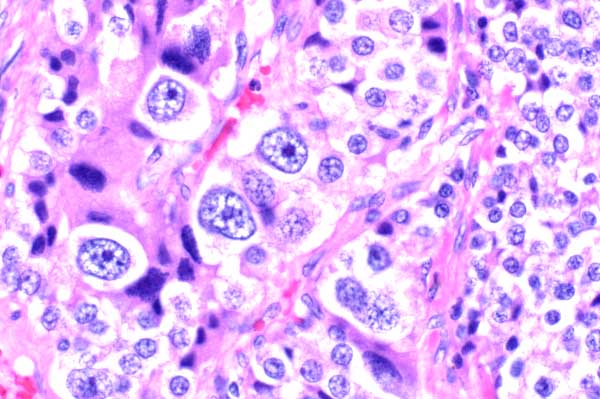

| 40x   |   Hematoxylin and Eosin | ||||

There is prominent anisocytosis and anisokaryosis, with rare cells having large nuclei with vesiculate chromatin and a large nucleolus.